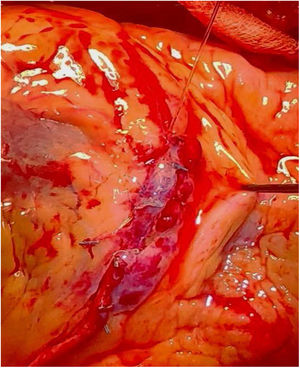

Bajo circulación extracorpórea y parada cardiaca mediante el uso de cardioplejía Del Nido, se procedió a la apertura longitudinal del segmento de DA ocupado por los stents previos, con extracción en bloque de todos ellos (fig. 2) empleando una técnica semejante a la de la endarterectomía coronaria (fig. 3A y B). La anastomosis distal con la arteria mamaria interna se preparó de manera que cubriese toda la arteriotomía de la DA, sirviendo de esta manera de parche de reparación (fig. 4). Se realizó un bypass con vena safena sobre la arteria descendente posterior. La desconexión de la circulación extracorpórea se llevó a cabo sin problemas, con flujometría por doppler correcta en ambos injertos. El tiempo de circulación extracorpórea fue de 78min, y el tiempo de pinzamiento aórtico de 39min.

El abordaje quirúrgico exige la planificación previa del procedimiento para establecer la zona a tratar, la longitud prevista de los stents a extraer, el material de reconstrucción de la arteria que se va a emplear, así como el injerto de revascularización que se quiere usar, etc. La técnica se lleva a cabo de manera semejante a una endarterectomía coronaria. Se realiza una arteriotomía longitudinal amplia, seguida de la separación cuidadosa del stent del endotelio arterial mediante la ayuda de una espátula de endarterectomía fina o un disector de Lemon. Se realiza una tracción suave de los stents hacia los segmentos proximal y distal de la arteria con ayuda de la espátula de endarterectomía para realizar contratracción e ir liberando la pared arterial (fig. 6). Posteriormente, se procede a la reparación de la arteria con el implante de un parche. Esto puede ser directamente realizado con la arteria mamaria (si esta es de buen calibre), realizando una apertura longitudinal amplia de la misma que cubra toda la arteriotomía realizada. En nuestro paciente se realizó una anastomosis amplia de la arteria mamaria interna sobre arteriotomía en la DA, previa extracción de los múltiples stents (fig. 7A). También puede realizarse la reconstrucción con parche de vena safena o pericardio. Si se opta por una de estas 2 últimas técnicas, posteriormente se realizará la anastomosis distal del injerto de revascularización sobre este parche, según la técnica de anastomosis habitual (fig. 7B)9,10.